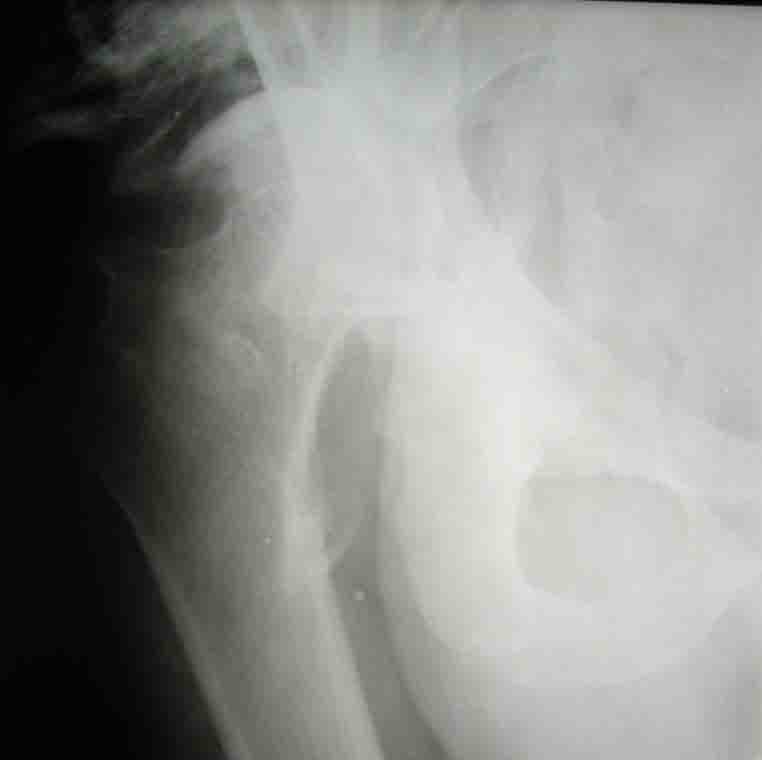

Уважаемые коллеги! На консультацию пришел молодой человек 23 лет с застарелым задним вывихомбедра. После травмы прошло 2,5 ГОДА.

Были переломы бедра и голени на этой же стороне, которые благополучно срослись после остеосинтеза. вывих бедра был пропущен. В настоящее время ходит без дополнительной опоры, есстественно, сильно хромает, выражен болевой синдром, парез седалищного нерва. Сформировался неоартроз в подвздошной области, виден неправильно сросшийся перелом задней колонны, сгибание в суставе до 80.